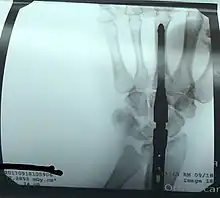

Radiographie après l’arthrodèse du poignet.

arthrodèse \aʁ.tʁo.dɛz\ féminin

- (Chirurgie) Fait de provoquer chirurgicalement l’immobilisation d’une articulation.